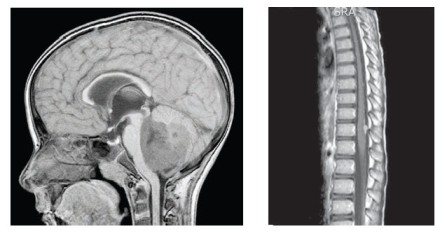

5-letý chlapec s negativní rodinnou anamnézou bez předchozích závažných morbidit se prezentoval příznaky intrakraniální hypertenze, poruchami zrakové ostrosti a nejistou chůzí. MRI mozku prokázala expanzivně se chovající nehomogenní tumor mozečku s nehomogenním sycením po kontrastu a s „polevovými“ míšnímu metastázami, tj. M3 nemoc, vysoké riziko (obr. 1,2). Pacient absolvoval totální exstirpaci primárního tumoru, histologicky byla potvrzena diagnóza meduloblastomu, desmoplastická varianta, bez amplifikace MYCC, MYCN (FISH vyšetření). Morfologický obraz tvořily uzly s buňkami se světlými jádry a s tmavými denzními jádry, polymorfní, mitoticky aktivní. Imunohistochemicky byla prokázána pozitivita synaptophysinu, mitotický index dle Ki67 byl 50 % a více. Zahájena byla léčba pro meduloblastomy vysokého rizika dle modifikovaného protokolu SJMB96 založená na kombinaci konkomitantní chemoradioterapie (temozolomid) s ozářením celé osy, dosycením na metastázy a zadní jámu, následovaly 4 cykly submyeloablativní chemoterapie s podporou autologních periferních kmenových buněk. Vzhledem k vysokému riziku nepříznivého průběhu nemoci jsme léčbu posílili cyklicky intraventrikulárně podávaným etoposidem cestou portu (Ommaya rezervoár). Intenzivní část protokolu pacient ukončil v parciální remisi.